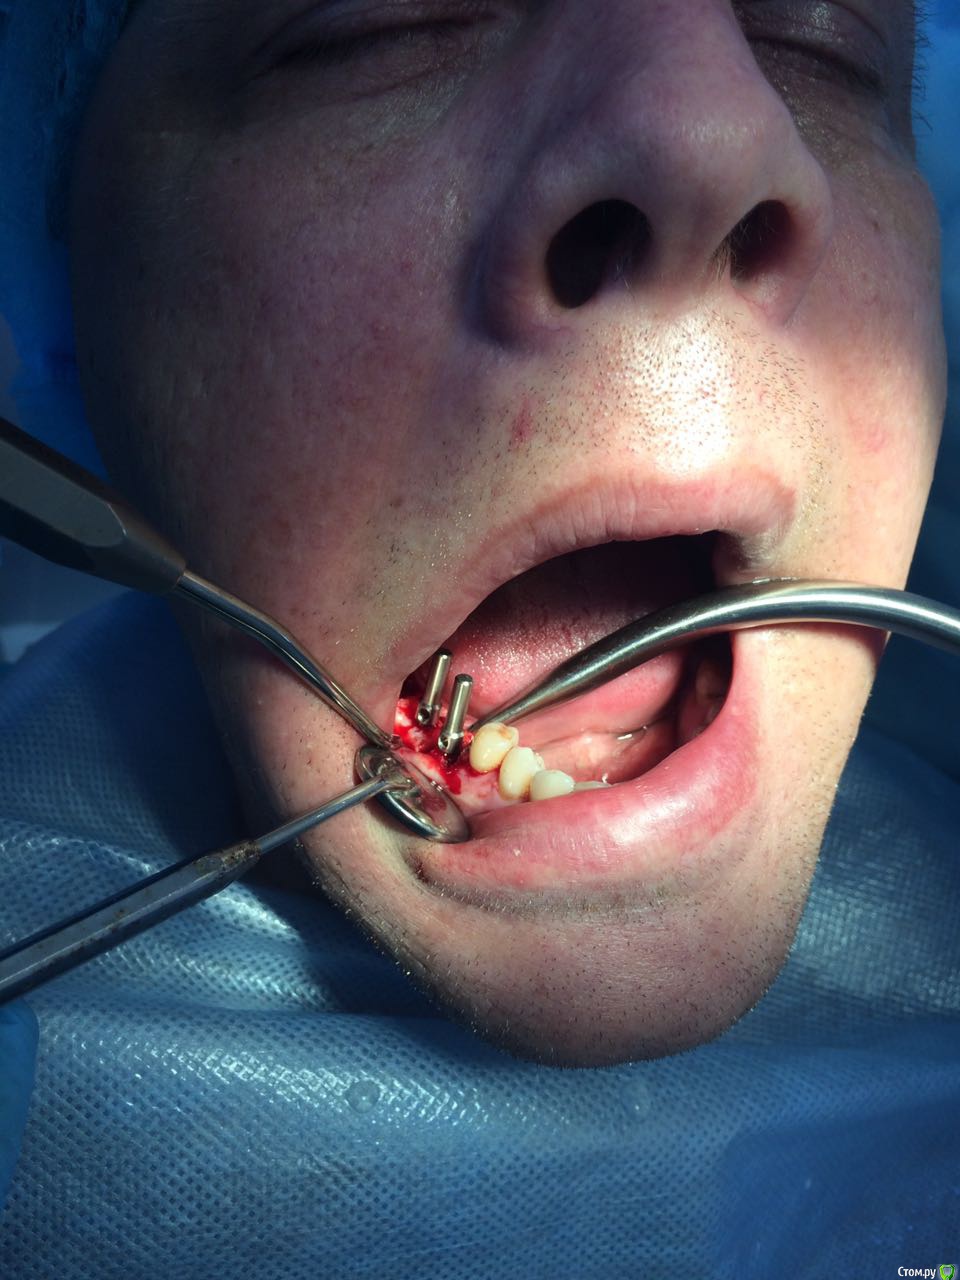

Пациент с жалобами на отсутствие 47 разрушение 46,48. После совещания с ортопедом и терапевтом принято решение удалять 46,48 и устанавливать импланты в позицию 46,47. post-48560-0-74269200-1490419709_thumb.jpgpost-48560-0-43642200-1490419772_thumb.jpgПрисутствует парадонтоз, лечение у пародонтолога прошел заранее. Решено было 46 ставить одномоментно, с графтом и мембранкой, 47 по стандартному протоколу, импланты alpha bio aic 4,2*12, 4,2*10 соответственно. post-48560-0-27512000-1490420040_thumb.jpgpost-48560-0-53003700-1490420066_thumb.jpg Сначала удалил, атравматично с распилом по бифуркации.post-48560-0-43340000-1490420143_thumb.jpgpost-48560-0-35881400-1490420170_thumb.jpgРаскрылся над 47, подготовил ложе, пины параллельности. Здесь вопрос, думаю зря широко отслоился и затронул 46?post-48560-0-32979400-1490420293_thumb.jpgpost-48560-0-94312700-1490420324_thumb.jpgустановка имплантов с фдм, графт в лунки 46 апатос, мембрана Эва. Снять не получилось. Нить моно 5-0. Тут опять вопрос фдм нужно было ставить шире? Но опять же импланты заглубил немного...post-48560-0-50977700-1490420493_thumb.jpg и контрольный. Конструктивная критика приветствуется)))